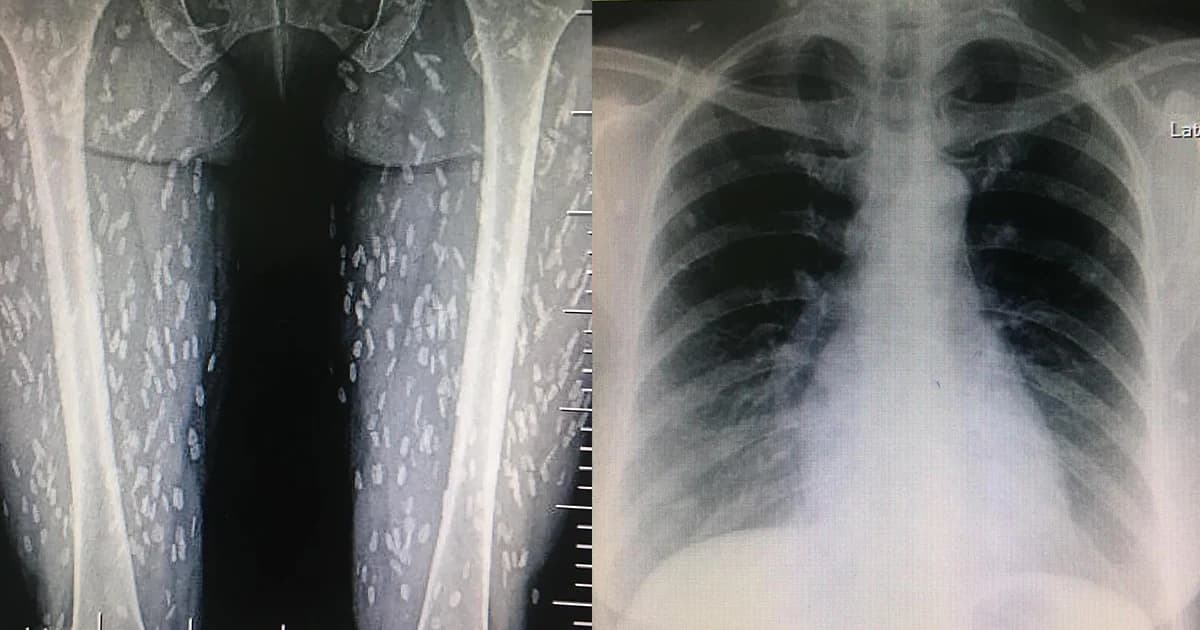

แชร์สนั่นโลกโซเชียล เมื่อคุณหมอโพสต์ภาพแผ่นฟิล์มเอ็กซเรย์คนไข้ พบในแผ่นฟิล์มเต็มไปด้วยจุดสีขาว ซึ่งเป็น ‘พยาธิตัวตืดหมู’ จากการกินอาหารสุกๆ ดิบๆ

วันที่ 5 ต.ค. 61 ผู้สื่อข่าวรายงานว่า สมาชิกเฟซบุ๊กชื่อ Kwang Volemage ได้โพสต์ภาพฟิล์มเอ็กซเรย์ของคนไข้รายหนึ่ง ซึ่งจากภาพเป็นแผ่นฟิล์มที่เต็มไปด้วยจุดสีขาวทั่วทั้งขาของผู้ป่วยคนนี้ โดยหมอสาวได้บอกว่า มันคือพยาธิตัวตืดโดยสาเหตุหลักมาจากการทานอาหาร ที่สุกๆ ดิบๆ ไม่ว่าจะเนื้อหมู เนื้อวัว และยังรวมถึงผักต่างๆ ที่ไม่ได้ล้างให้สะอาดอีกด้วย และโพสต์ระบุข้อความไว้ดังนี้

“cc : หายใจลำบาก คอไม่โล่ง มีเสมหะในคอ O2sat 98% lung – clear pharynx not inject me : คิดในใจไป CXR หน่อยก็ได้ แล้ว film ก็มา เลยไป film femur ต่อตามคำแนะนำ Supanat Boonneramitr #อึ๊ยขนลุก #cysticercosisจากหนังสือมาสู่ของจริง #พยาธิตืดหมู” คาดว่า เป็นเคสที่เกิดขึ้นที่โรงพยาบาลพรานกระต่าย ที่อยู่ 114 หมู่ 11 ต.พรานกราะต่าย อ.พรานกระต่าย จ.กำแพงเพชร

สำหรับสาเหตุ เบื้องต้นที่พยาธิตืดหมูเข้าสู่ร่างกาย เกิดจากการกินเมนูที่ใส่หมูดิบแล้วมีตัวอ่อนพยาธิในนั้น หรือกินผักที่ปนเปื้อนไข่ของพยาธิชนิดนี้ พอตัวอ่อนไชเข้าร่างกาย ก็จะไปแถวกล้ามเนื้อ หรือเข้าสมอง จากนั้นก็จะกลายเป็นหินปูนดังภาพที่ปรากฏ แล้วทำให้เกิดอาการต่างๆ โดยเฉพาะหากขึ้นสมอง ก็จะมีอาการปวดหัวเรื้อรัง หรือชักเกร็ง เป็นต้น